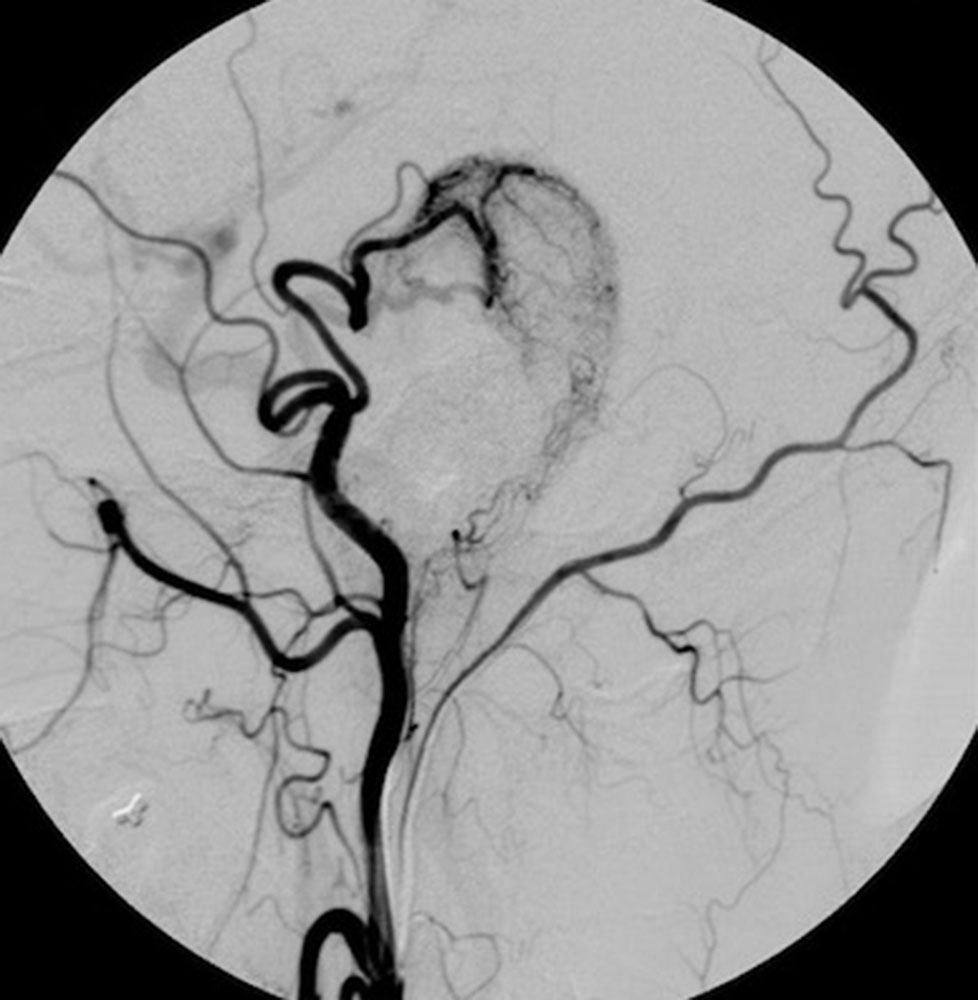

The protruding and pulsating ear was an unbearable condition for the patient. The increase in size did not begin until adolescence. The angiography demonstrates the large-caliber feeding vessel, which is also striking during surgery. The nidus was resected in toto, and the wound was primarily closed. An anterior approach was used to reduce the size of the helix in the same session.